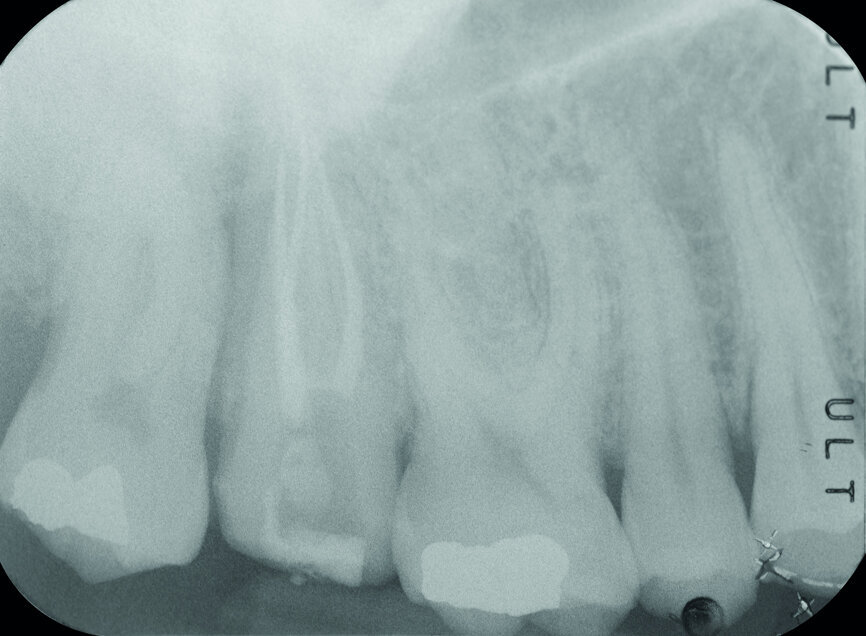

Fig. 3: Pre-op periapical radiograph.

A 47-year-old male patient in a good medical condition and a non-smoker was referred to our dental practice for endodontic retreatment of the right maxillary second molar. The dental history revealed that the tooth had been endodontically treated three months before because of acute pulpitis. After the treatment, the patient complained of pain on chewing. Antibiotics and a non-steroidal anti-inflammatory drug were prescribed, but the pain remained. After a month, a sinus tract appeared. The tooth was retreated in another practice without success. The clinical inspection revealed the presence of a sinus tract near the apical region of tooth #17. The tooth had been prepared for a full crown, but was without even a temporary crown, and the access cavity had been closed with temporary filling material. Cracks were evident on the buccal and mesial surfaces. Periodontal probing showed a deep pocket (> 12 mm) on the distal aspect of the root trunk (Figs. 1 & 2). The periapical radiograph showed a radiolucency between the roots of the second and third molars. The radiographic appearance of the endodontic treatment was good, without clear evidence of periapical radiolucencies (Fig. 3). A perforation of the pulp chamber floor was suspected. A CBCT scan was performed (Figs. 4–7), and it confirmed the suspicion of perforation, along with the presence of a large periradicular radiolucency and an unfavourable root shape.